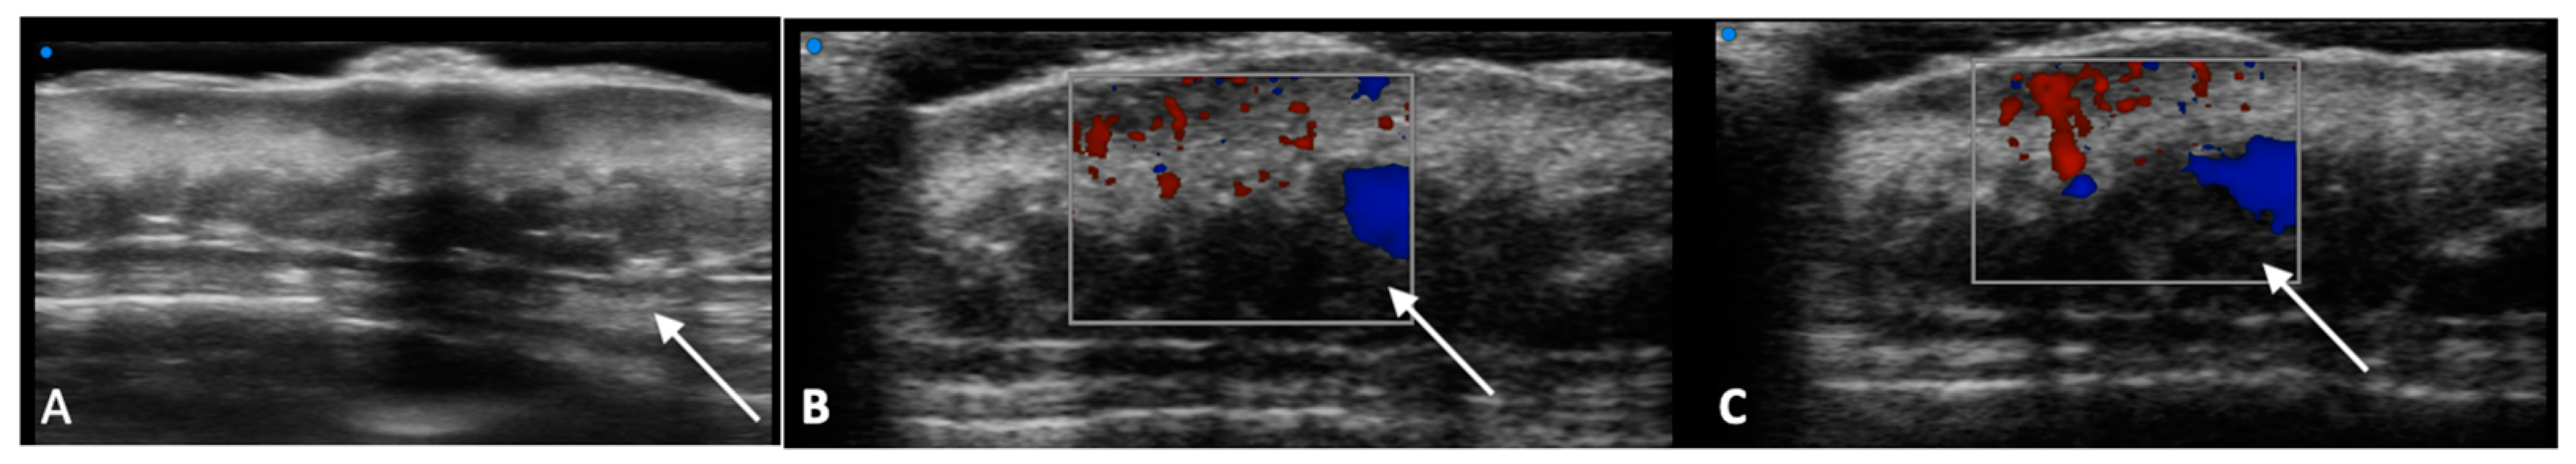

- Catalano, O.; Roldán, F.A.; Varelli, C.; Bard, R.; Corvino, A.; Wortsman, X. Skin cancer: Findings and role of high-resolution ultrasound. J. Ultrasound 2019, 22, 423–431. [Google Scholar] [CrossRef] [PubMed]

- Wang, S.-Q.; Liu, J.; Zhu, Q.-L.; Zhao, C.-Y.; Qu, T.; Li, F.; Wortsman, X.; Jin, H.-Z. High-frequency ultrasound features of basal cell carcinoma and its association with histological recurrence risk. Chin. Med. J. 2019, 132, 2021–2026. [Google Scholar] [CrossRef]

- Reginelli, A.; Belfiore, M.P.; Russo, A.; Turriziani, F.; Moscarella, E.; Troiani, T.; Brancaccio, G.; Ronchi, A.; Giunta, E.F.; Sica, A.; et al. A Preliminary Study for Quantitative Assessment with HFUS (High- Frequency Ultrasound) of Nodular Skin Melanoma Breslow Thickness in Adults Before Surgery: Interdisciplinary Team Experience. Curr. Radiopharm. 2020, 13, 48–55. [Google Scholar] [CrossRef]

- Belfiore, M.P.; Reginelli, A.; Russo, A.; Russo, G.M.; Rocco, M.P.; Moscarella, E.; Ferrante, M.; Sica, A.; Grassi, R.; Cappabianca, S. Usefulness of High-Frequency Ultrasonography in the Diagnosis of Melanoma: Mini Review. Front. Oncol. 2021, 11, 673026. [Google Scholar] [CrossRef]